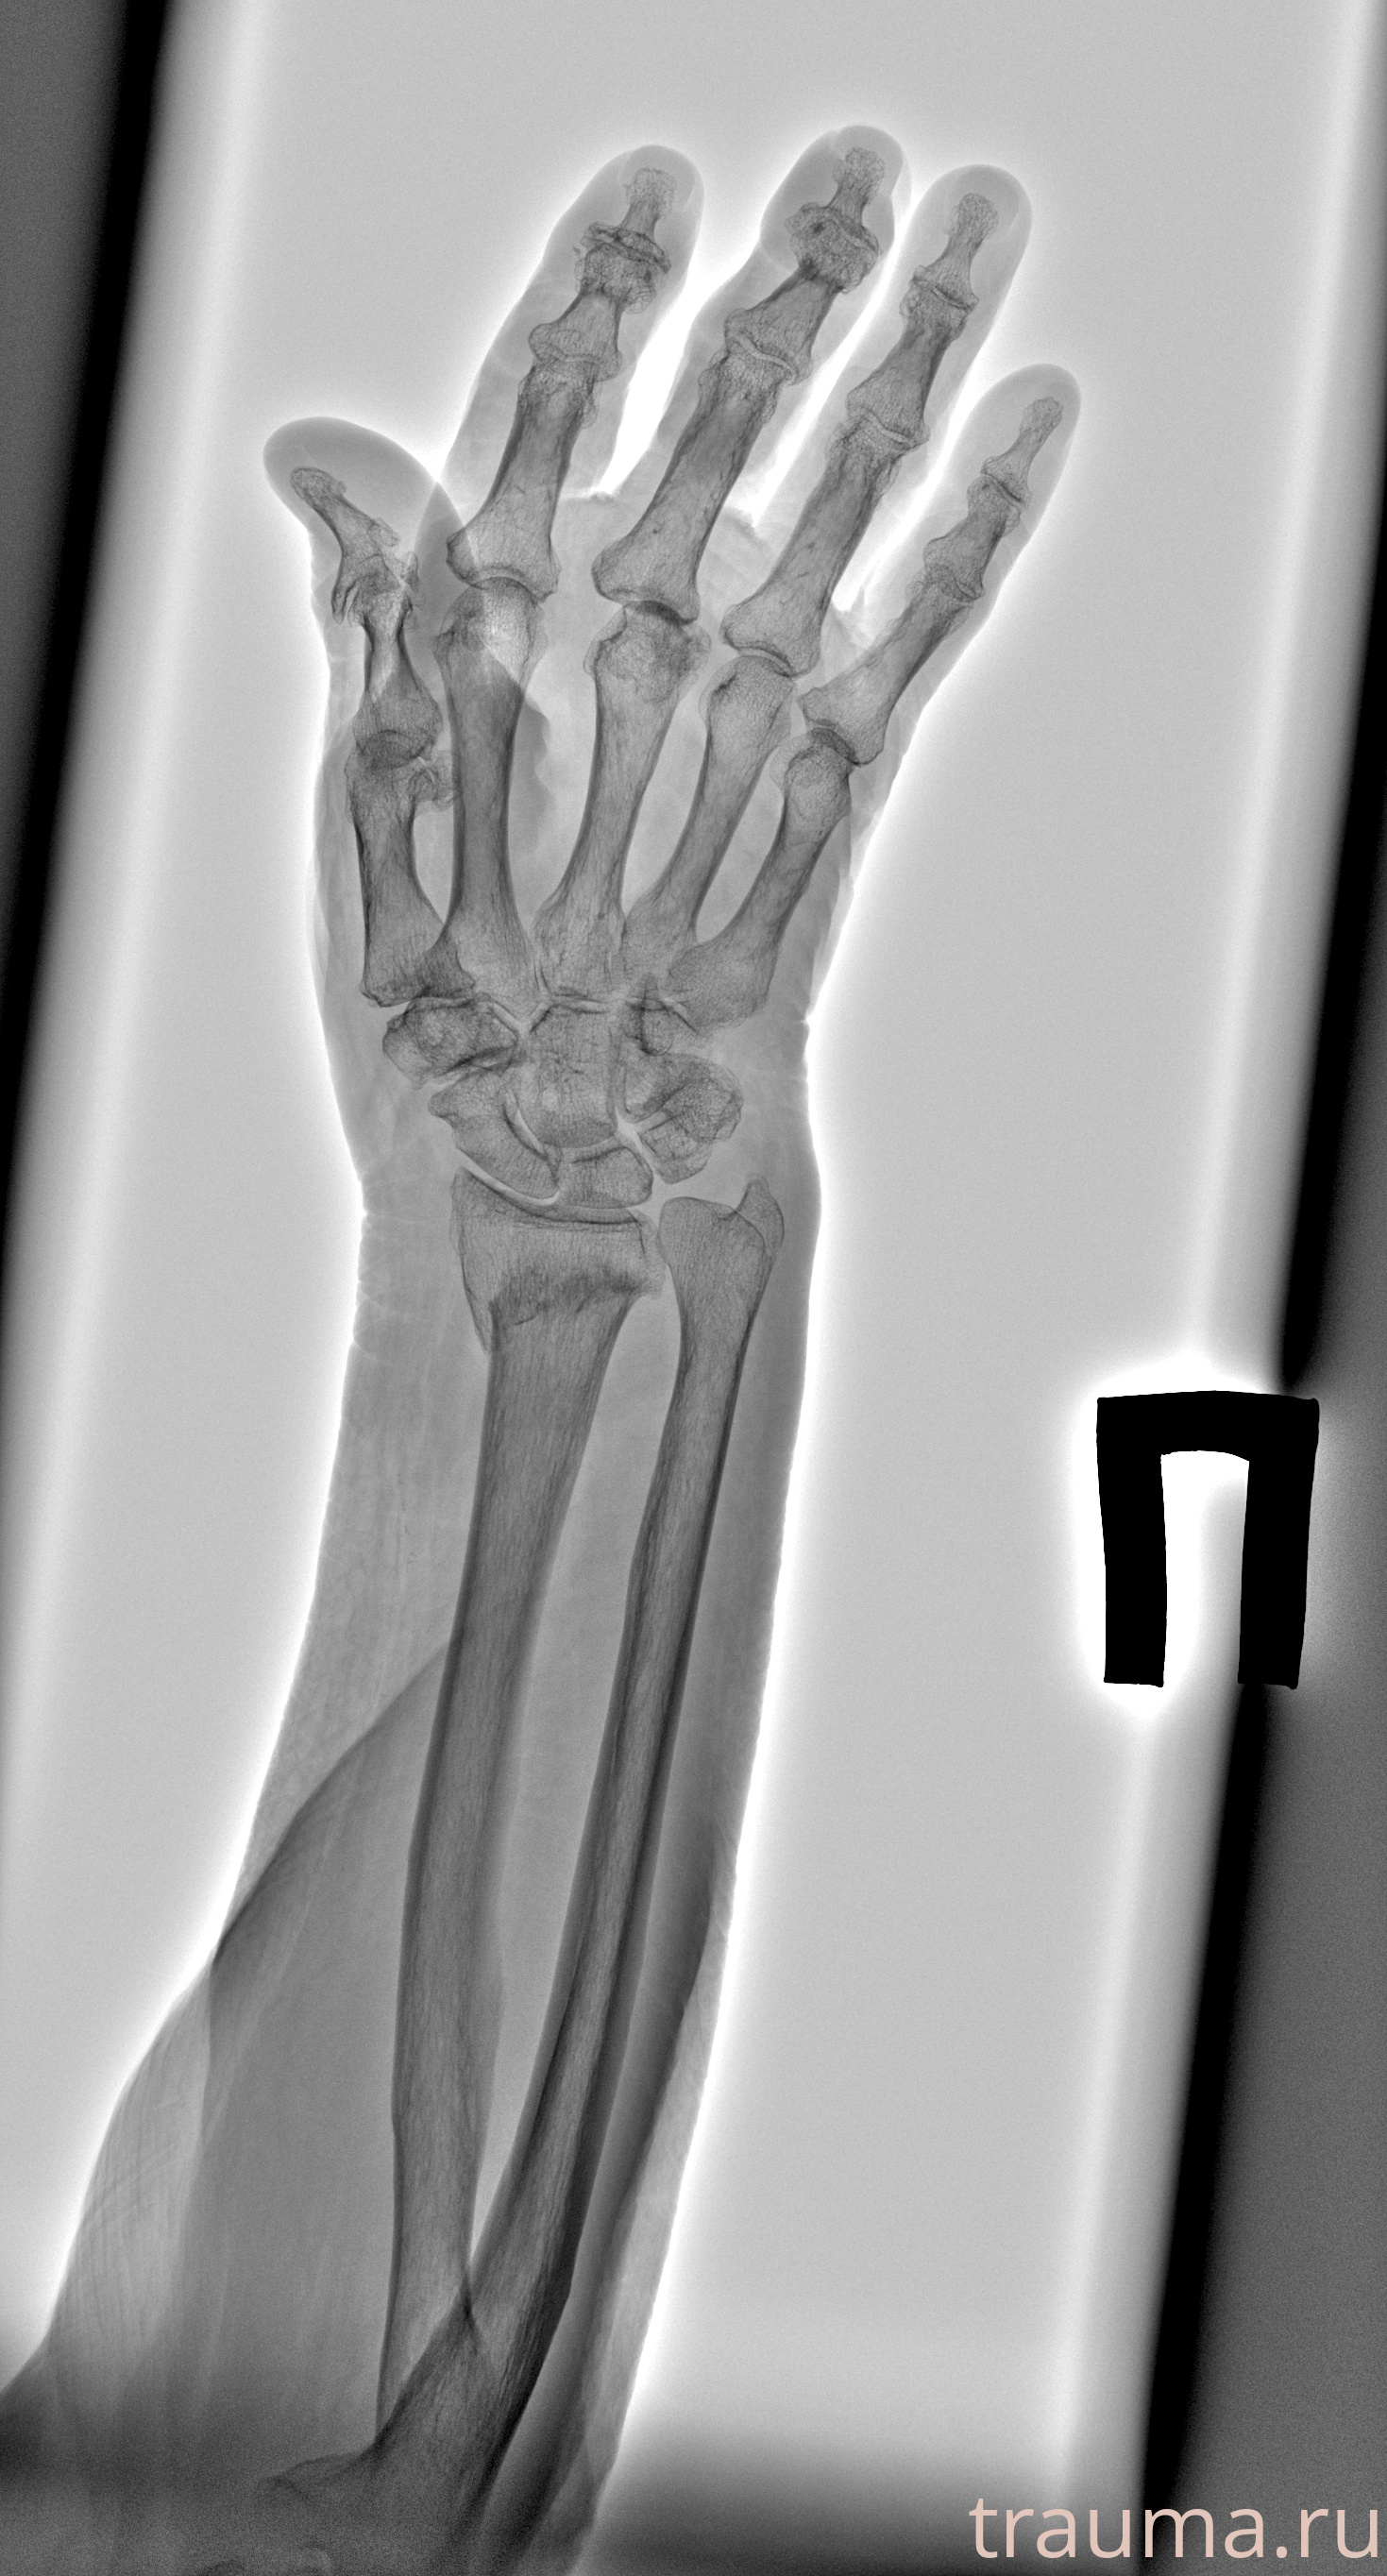

Рентгенограммы

Рентген на дому: по вашему адресу приезжает врач-рентгенолог, травматолог-ортопед с мобильным рентгеновским аппаратом, проводит диагностику травмы или заболевания, делает необходимые рентгенограммы, дает рекомендации по дальнейшему лечению. Получить качественные снимки в домашних условиях возможно благодаря уникальной методике, разработанной МосРентген Центром для института  Склифосовского